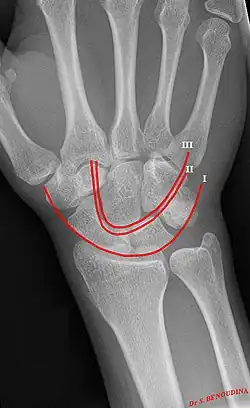

Gilula's lines are three arcs drawn on an AP radiograph of the wrist used to assess the alignment of the carpal bones.[1] They were first described by Louis A. Gilula in 1979.[2]

There should be no step-off in the contour of the lines when drawn on a normal wrist.

| First arc | running along the proximal convexity of the scaphoid, lunate and triquetrum |

| Second arc | running along the distal concavities of the scaphoid, lunate and triquetrum |

| Third arc | running along the proximal curvatures of the capitate and hamate |